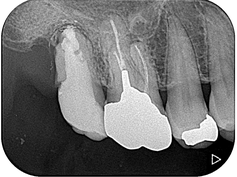

8か月後の経過観察になります。根尖部の透過像は大幅に縮小していることが確認できます。患者さんの自覚症状もなく、良好に経過しております。抜歯しなくて大丈夫だったことを大変喜ばれておりました。